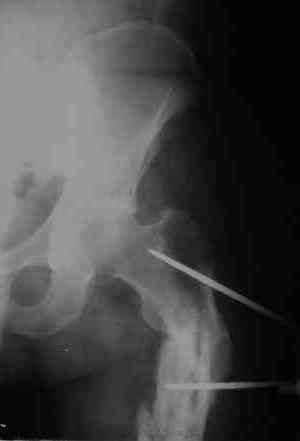

Уважаемые коллеги! Пришел на консультацию вот такой больной (первые 3-и рисунка). Травма автодорожная, апрель 2006г. Лечился консервативно, вытяжение и гипс. Через пять месяцев стал ходить. Укорочение бедра 6 см. 26 февраля 2007г. оступился, упал. Прооперирован в г.Баку - наложен стержневой аппарат. Ходит с костылями, наступая на левую ногу.

Мы попросили что нибудь из ранних снимков. Принес рентгенограммы перелома (рис. 4,5). Посмотрели, наснимали сами (рис. 6-10). Похоже, что нет сращения нигде. Хотелось - бы обсудить следующие вопросы: 1. дальнейшая тактика - реостеосинтез или подождать (ослабить аппарат, дать нагрузку и т.д.)? 2. если реостеосинтез - то чем и как? Юрий Алексеевич Булахтин